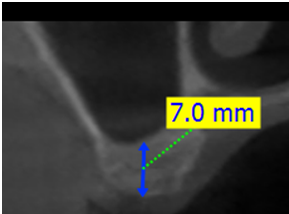

1. 首先由X光片先確認鼻竇下的骨頭高度,照一般的drill程序先將鼻竇以上的骨修形做好(當然也要考量骨質密度決定要擴大到何種程度)。

2. 由於即使是斷層,一樣會有10%的變形率,而且由於鼻竇底部可能是斜面,所以難以掌控何時鼻竇底部破掉的正確位置。假設案例為鼻竇下有7mm骨高度,我們先完成6mm深度的骨修型,接者就可以拿出廠商所附的reamer (800-1200 rpm)與stopper ; 這個stopper 和手術盒內的組件都可以接在一起,藉由6mm的stopper我們能夠往下鑽的reamer的深度就不可能超過6mm,測試看看鼻竇底部有沒有破掉?破掉時會感覺阻力突然變小,因為被stopper限制住能進入的深度,所以並不會因為阻力突然變小,reamer就突然下鑽過深,造成鼻竇黏膜破掉; 假若沒有破掉, 接著可以更換成7mm, 8mm ...的stopper,直到感覺鼻竇底部已穿破; 由於一次只加1mm,且reamer的底部較圓鈍, 骨碎屑會卡在reamer間隙內, 所以不易造成深度突然過深而造成鼻竇黏膜破掉的問題。